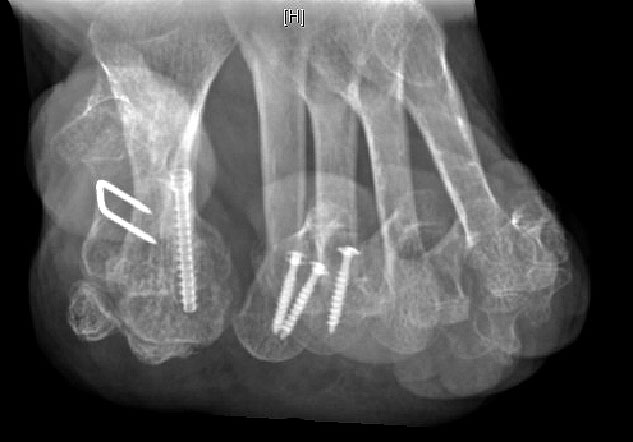

Gute Ergebnisse werden in diesem Fall durch die Arthrodese des MTP-1-Gelenkes erzielt. Bei älteren Patienten kann zum Erhalt der Beweglichkeit eine Keller-Brandes-Prozedur sinnvoll 2327, (Wirth, 2002)

Arthrodese MTP I und weichteilige Rezentrierung MTP II und III (eigenes Bildmaterial)

Abbildung 18